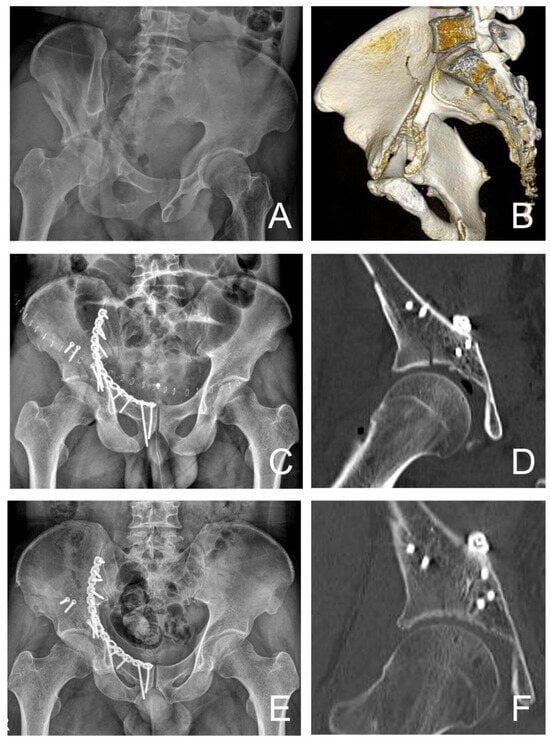

| Postoperative reduction status | |||

| Anatomical (<1 mm) | 12 | 13 | >0.05 |

| Congruent (2–3 mm) | 7 | 9 | >0.05 |

| Poor (>3 mm) | 1 | 7 | >0.05 |

| Medialization of femoral head (mm) | 0.3 | 3.9 | <0.05 * |